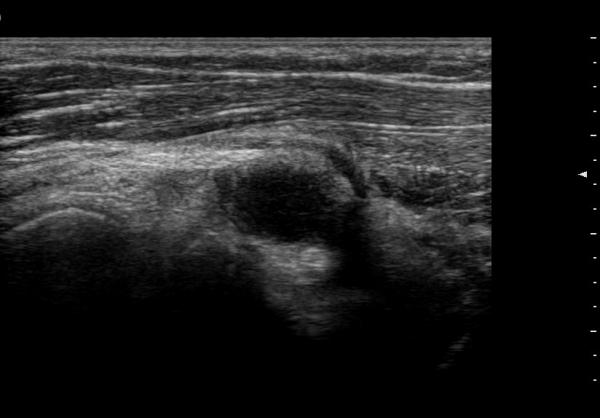

ŽÃËÀÚ¸¦ ¸»´ÜÀ¸·Î À̵¿ÇÏ´Ï ¿ä°ñµÎ ºÎÀ§¿¡¼­ Àú¿¡ÄÚ ³¶Á¾ÀÌ Èİñ°£½Å°æºÐÁö¸¦ Ç¥ÃþÀ¸·Î

ÀüÀ§½Ã۰í ÀÖ´Ù(±×¸² 2, 3,)